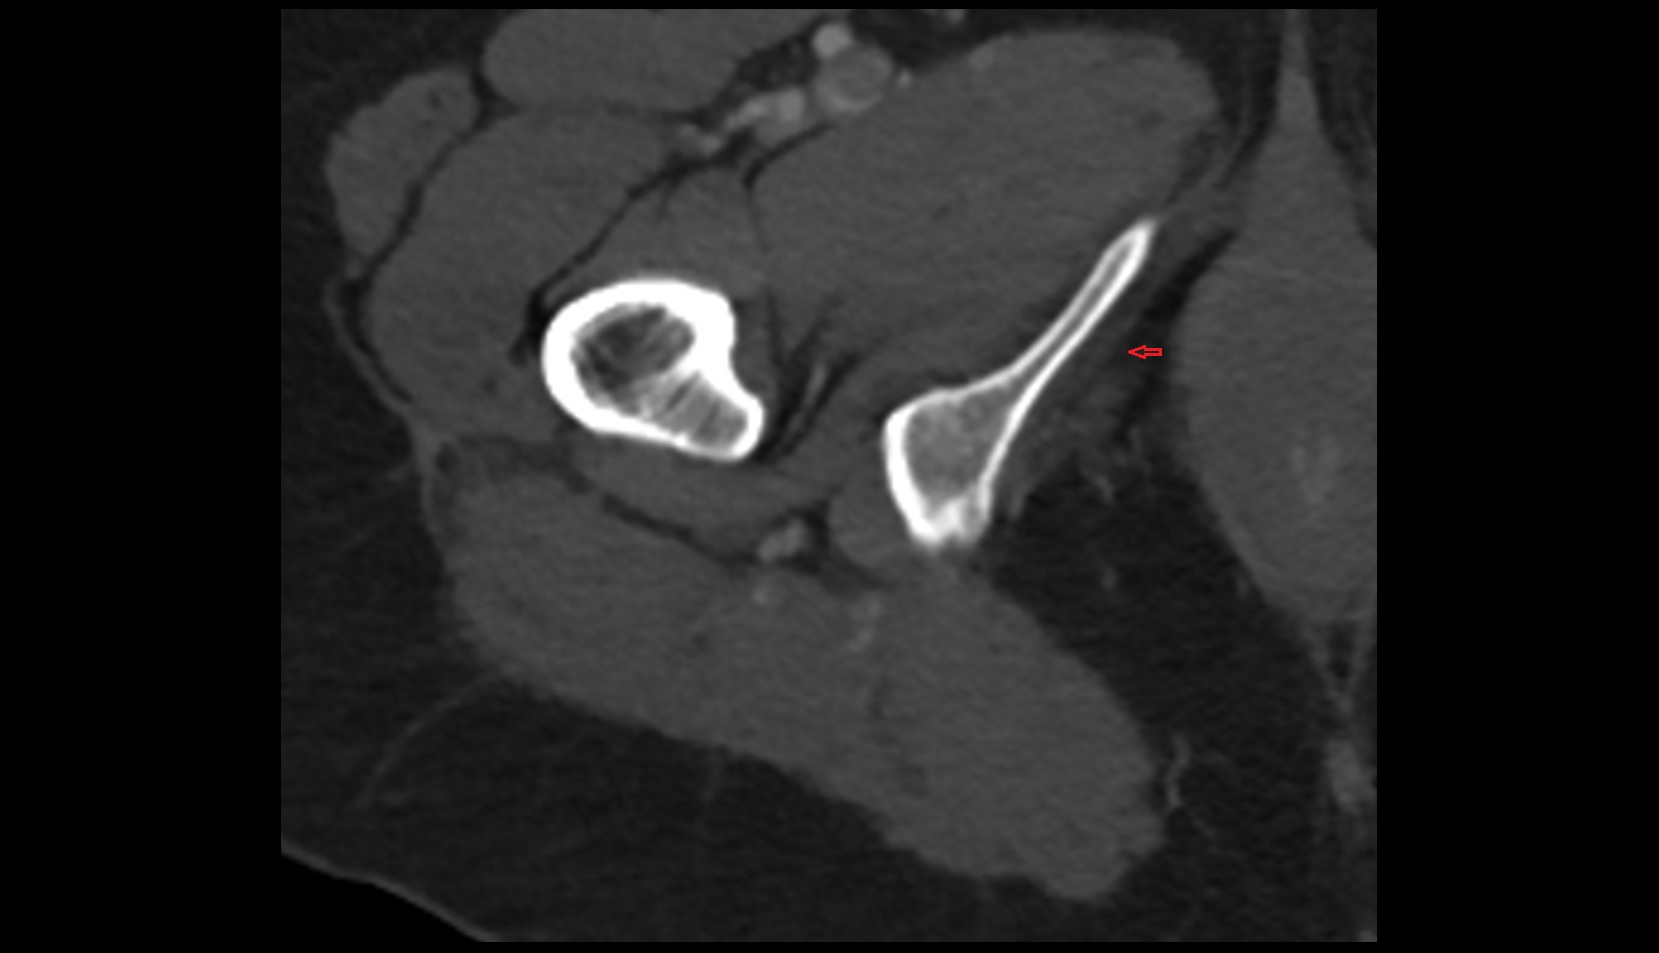

- Hip joint

- Head of femur

- Neck of femur

- Acetabulum